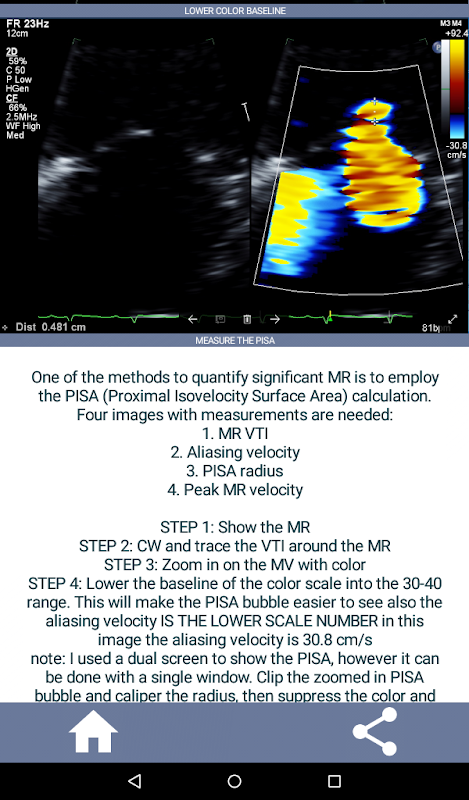

Learn the full echo ultrasound protocol that meets and exceeds the IAC Standards and Guidelines for Echocardiography Accreditation. Just starting to learn echocardiography or need a quick refresher for that echo job interview? This app will quickly get you up speed on the full TTE (transthoracic echocardiogram) protocol currently used in a major hospital from a practicing echo technologist's point of view while also providing the starting cardiac sonographer with a concise, detailed "how to" guideline on a complete echo exam. The app consists of over 90% video clips displaying proper views and also showing the most common abnormal cardiac pathology (e.g. aortic stenosis) that an echo tech will likely encounter and what to do.